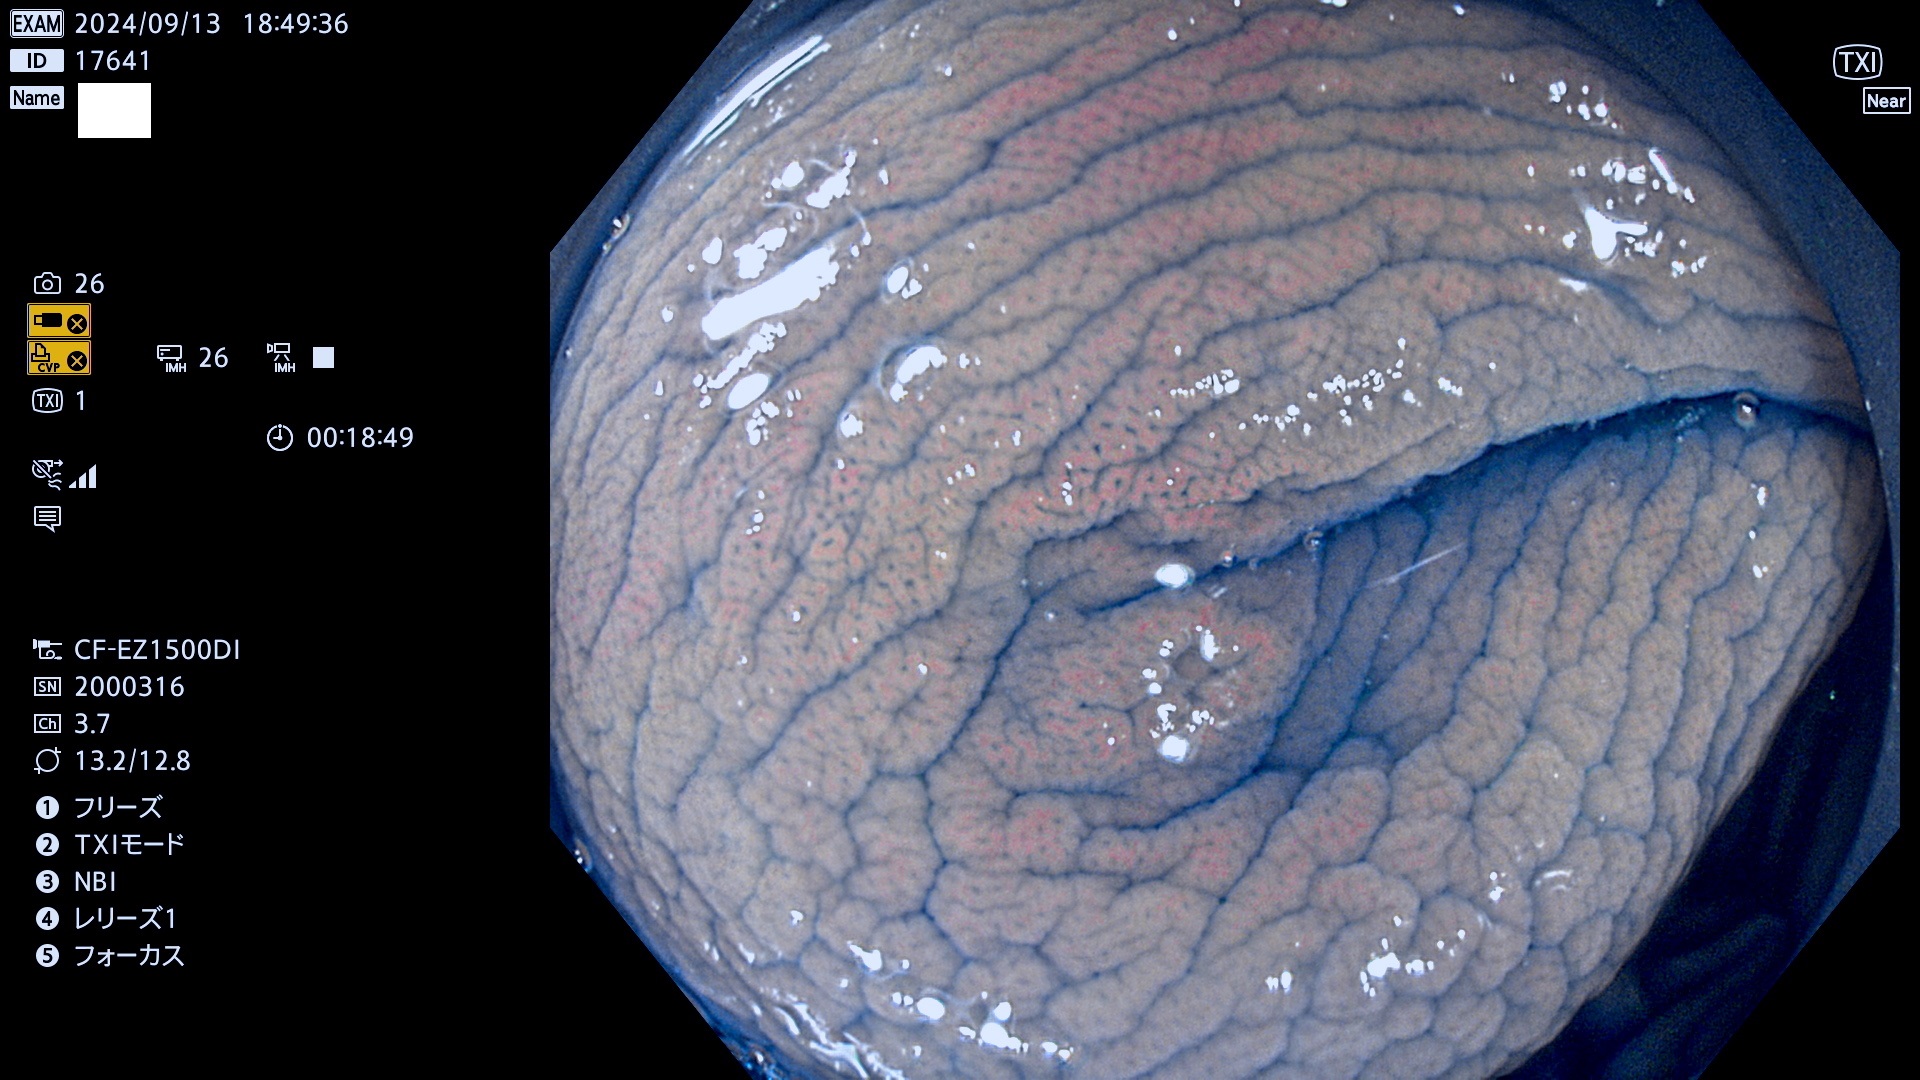

完全に平坦な物をUb、陥凹している物をUcと呼びます。最も発見が難しく危険な病変です。

毎週の検査(木・金・土・日)に発見されたUb、Uc型・腺腫を、その週の日曜の夜にUPし1週間、提示します。

抽出の対象期間 2024年9月12日〜9月15日の4日間(45件の検査)9件 (9/45=20%)